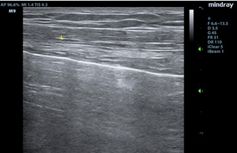

D1.

D2.

D3.

Figure D. In image D1, the TE7 Ultrasound machine is looking at the inferior vena cava (IVC). Image D2 shows the lung with ultrasound and D3 shows a cardiac assessment with smart measurements to check heart function. Images courtesy of Mindray Medical International.